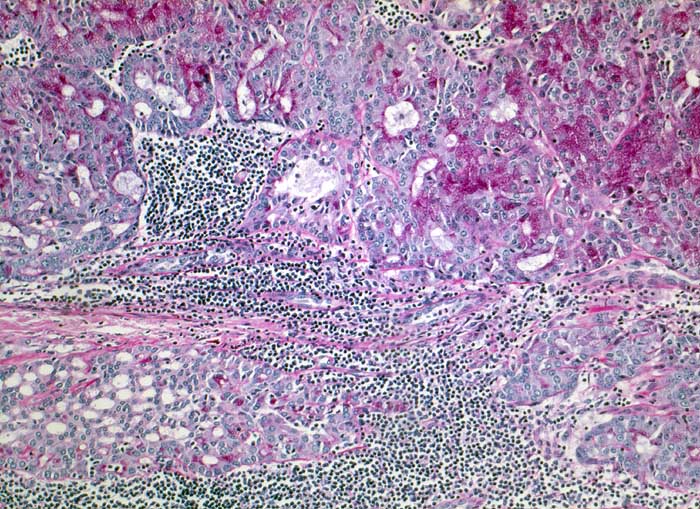

Azinuszellkarzinom der Parotis

Azinär differenzierte Tumorzellen mit reichlich Diastase-PAS positivem Zytoplasma. Teils follikuläres, teils mikrozystisches Wachstumsmuster. Reichlich lymphoides Stroma.

Tumorzellen fokal Amylase und Diastase-PAS positiv

Azinuszellkarzinome sind nach den Mucoepidermoidkarzinomen und den nicht näher spezifizierten Adenokarzinomen die häufigsten malignen Speicheldrüsentumoren und am häufigsten bilateral (3%). Azinär differenzierte Zellen können oft nur eine Minderheit ausmachen. Daneben gibt es auch kubische Zellen vom Streifstücktyp oder Zellen eines Adenokarzinoms ohne spezielle Differenzierung. Azinuszellkarzinome können viele Wachstumsmuster zeigen: mikrozystisch, solide, follikulär, papillär zystisch, glandulär. Typisch, aber nicht spezifisch ist ein ausgeprägtes lymphoides Stroma (keine echten Lymphknoten), welches zur richtigen Diagnose führen kann. Die Azinuszellen enthalten Diastase PAS positives Material und sind immunhistochemisch positiv für Amylase (oft nur herdförmig).

Histologie

630